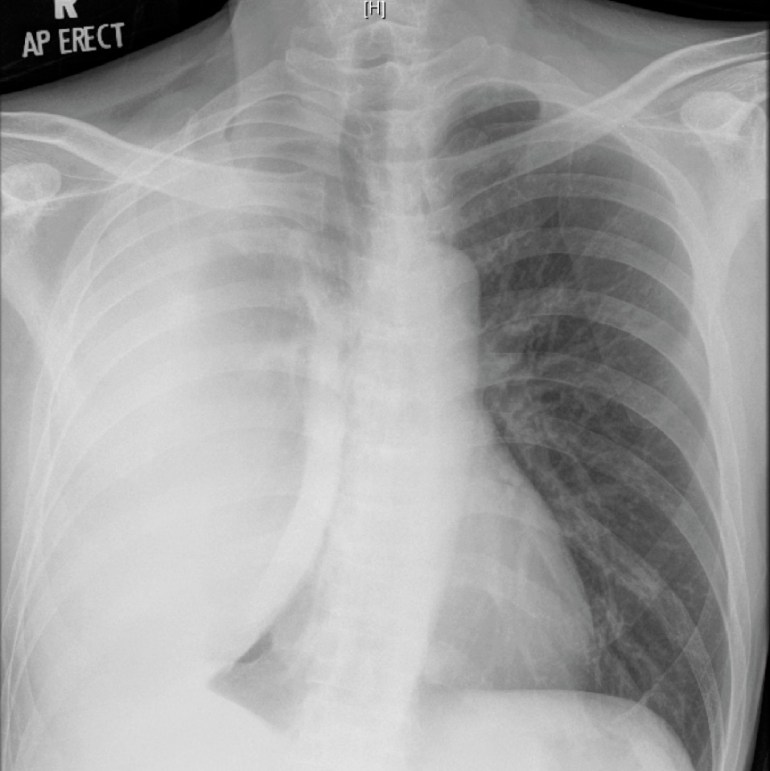

This patient had a loculated pleural effusion with radiological suggestion of a trapped lung. However, the massive increase in size of the pleural effusion 2 months after starting appropriate treatment is consistent with a paradoxical response to anti-tuberculosis therapy. This is now believed to be a immune reconstitution syndrome, and occurs in up to 15% of non-HIV patients but up to 25% of HIV-infected patients with concurrent tuberculosis who are started on highly-active anti-retroviral therapy (HAART). It occurs more commonly with extra-pulmonary tuberculosis, particularly cervical lymphadenitis and TB pleurisy.

Treatment of paradoxical response to anti-tuberculosis therapy is largely conservative, although steroids and/or surgical therapy are options if symptoms are severe. We offered the patient surgical drainage of the effusion in view of its massive size (potentially complicating respiratory function should any new lung infection develop), but he wisely refused. Subsequent chest X-rays showed gradual reduction in the size of the effusion over time, although it did not really disappear even at the time of stopping anti-tuberculosis therapy.